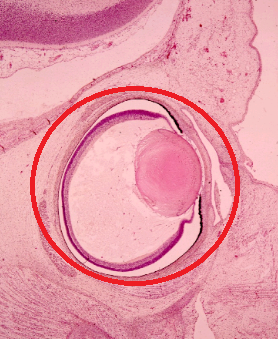

Question 7

Question

Marque la opción que corresponde a la estructura señalada

Image:

3a996a72-a62b-46b0-9ad3-bc26f3cad23f (image/png)

Answer

Proceso ciliar

Cristalino

Córnea